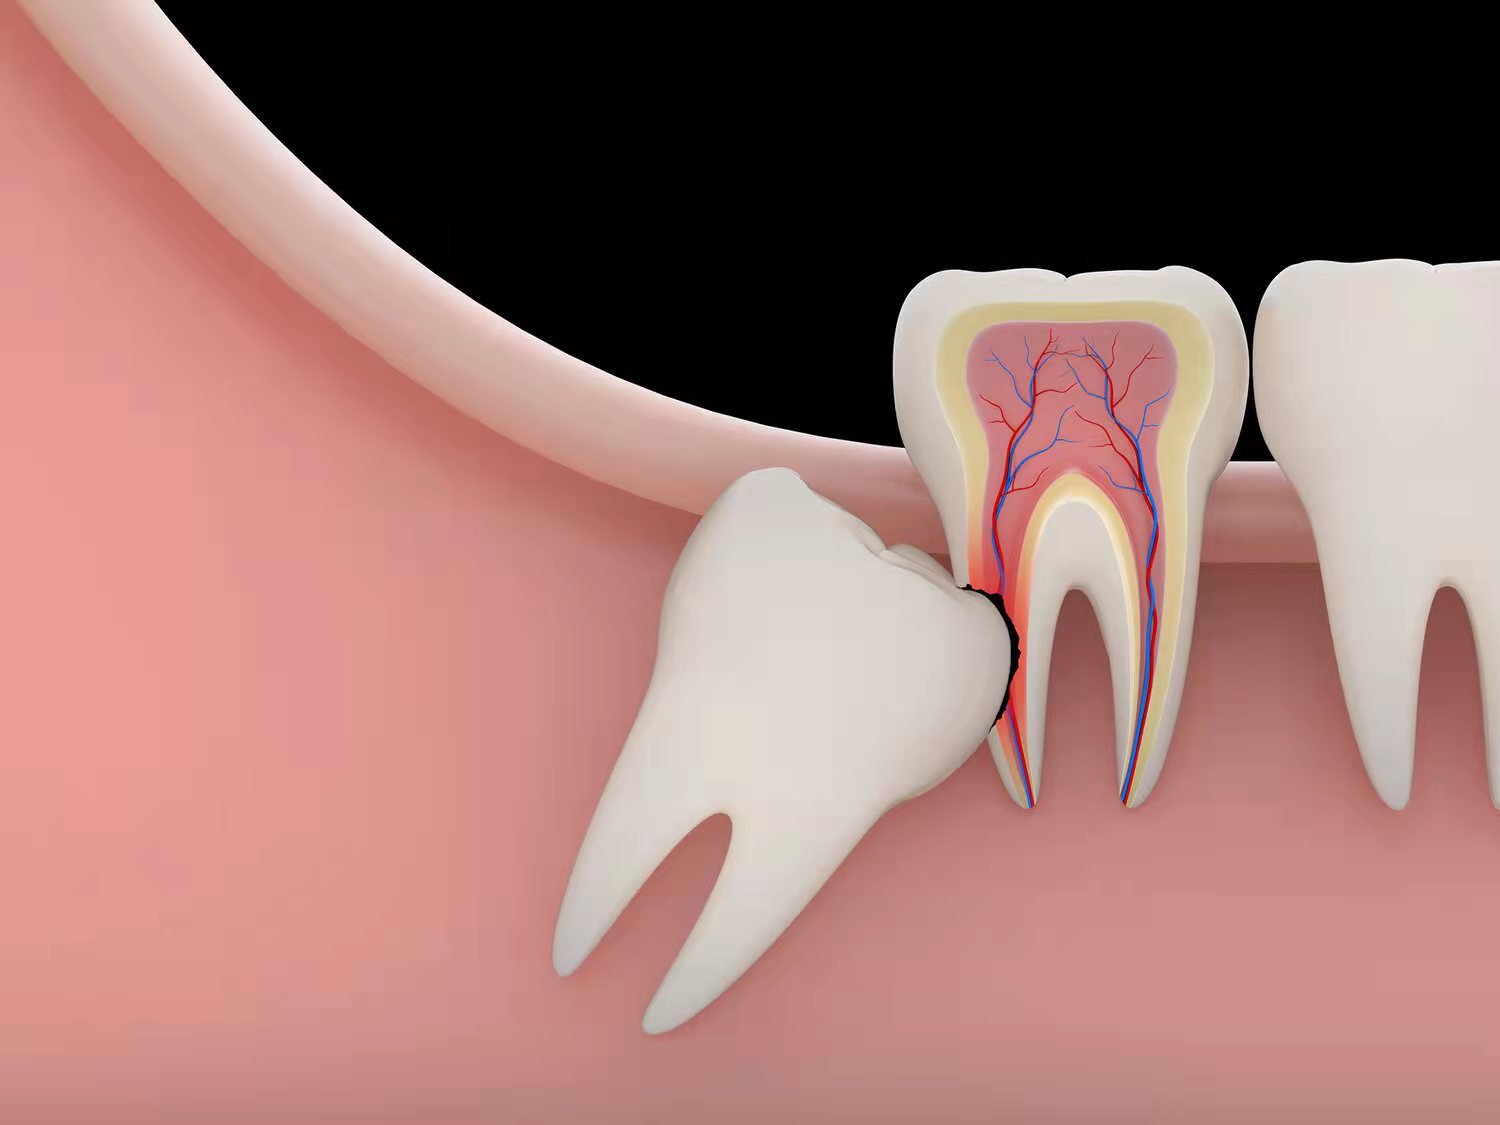

②反复发炎

大部分去拔智齿的人,都是因为被反反复复的炎症折磨得痛苦难耐。当牙齿和牙龈缝隙里经常有食物残渣时,就很难清洁。长期如此,就会诱发冠周炎。炎症往往比较难控制,肿胀和疼痛让人叫苦不迭,这时候就必须去拔了。[2]

③影响其他牙齿

智齿在出现过程中,经常会影响到周围的牙齿,甚至会把周围本来好好的牙齿给顶坏了,这个时候也必须拔除。